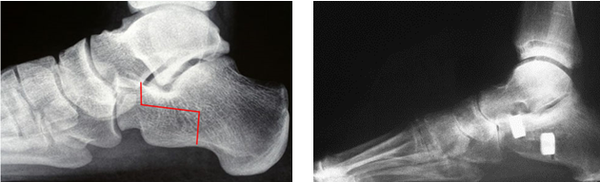

Rotational calcaneal osteotomy

This procedure combines some of the advantages of the Evans and the MDCO providing an increased ability to realign severe mal-alignment without fusing any joints.

There remains the risk in the adult patient of developing arthritis in other foot joints, depending on how well the individual adapts to the foot being repositioned. Other risks include nerve and tendon irritation due to the increased dissection and the proximity of these structures.

(Pre and post X-rays showing the line of the bone cuts and subsequently view post procedure with the calcaneum lengthened and rotated at the same time)

Hoke (Navicular cuneiform fusion)

The pathological flat foot tends to sag at the navicular cuneiform joints. Given time the loss of alignment is fixed, often with arthritis present. Taking a wedge to correct the arch and reduce the instability is a common adjunctive procedure providing good stability to the arch.

These X-rays show the foot from the side with initially a loss of arch height and a midfoot sag, in a young adult. Post procedure the lateral column has been lengthened using an Evans procedure with a navicular cuneiform fusion.

This has now been successfully realigned.